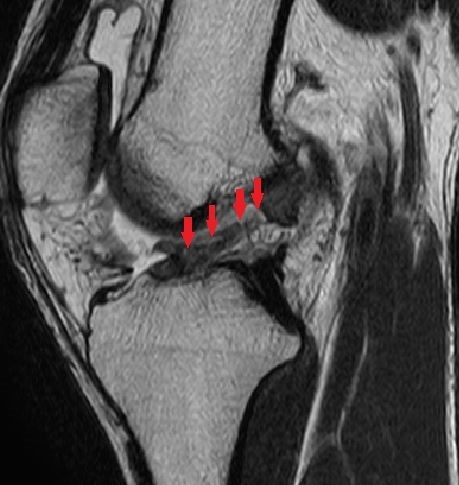

MRI画像①

大腿骨内顆・外顆に骨挫傷

②

脛骨後顆に骨挫傷

③

前十字靭帯が不明瞭